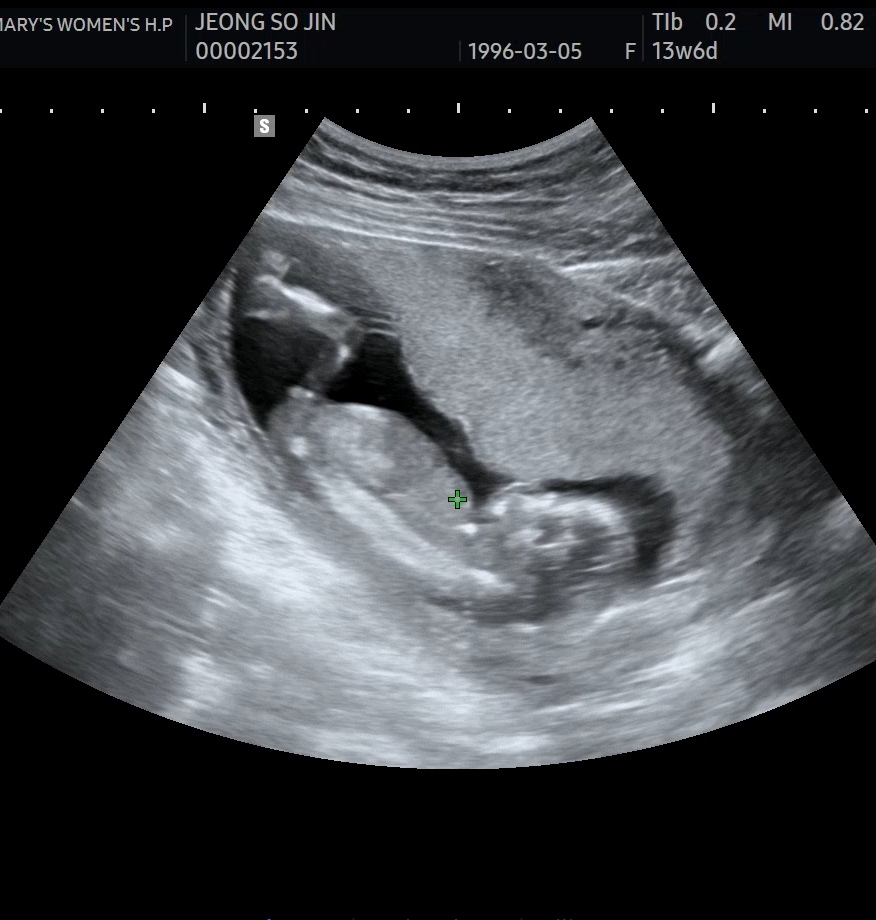

뭔가보이는데 탯줄일까요?

각도법으로보면 딸같기도하고...